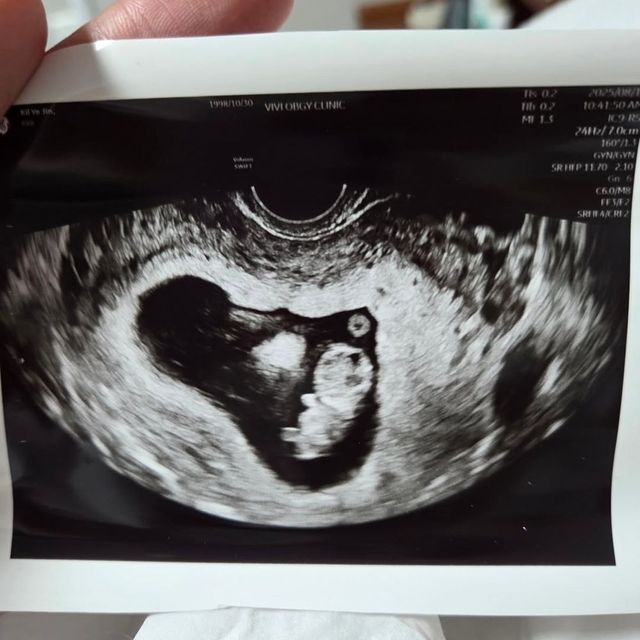

이어 김동재는 “오는 3월 우리 부부에게 아들이 찾아온다”며 기쁨을 감추지 못했다. 그는 “행복하게 잘 살겠다. 많은 분들의 응원 부탁드린다”고 덧붙이며 팬들과 지인들에게 감사의 인사를 전했다.